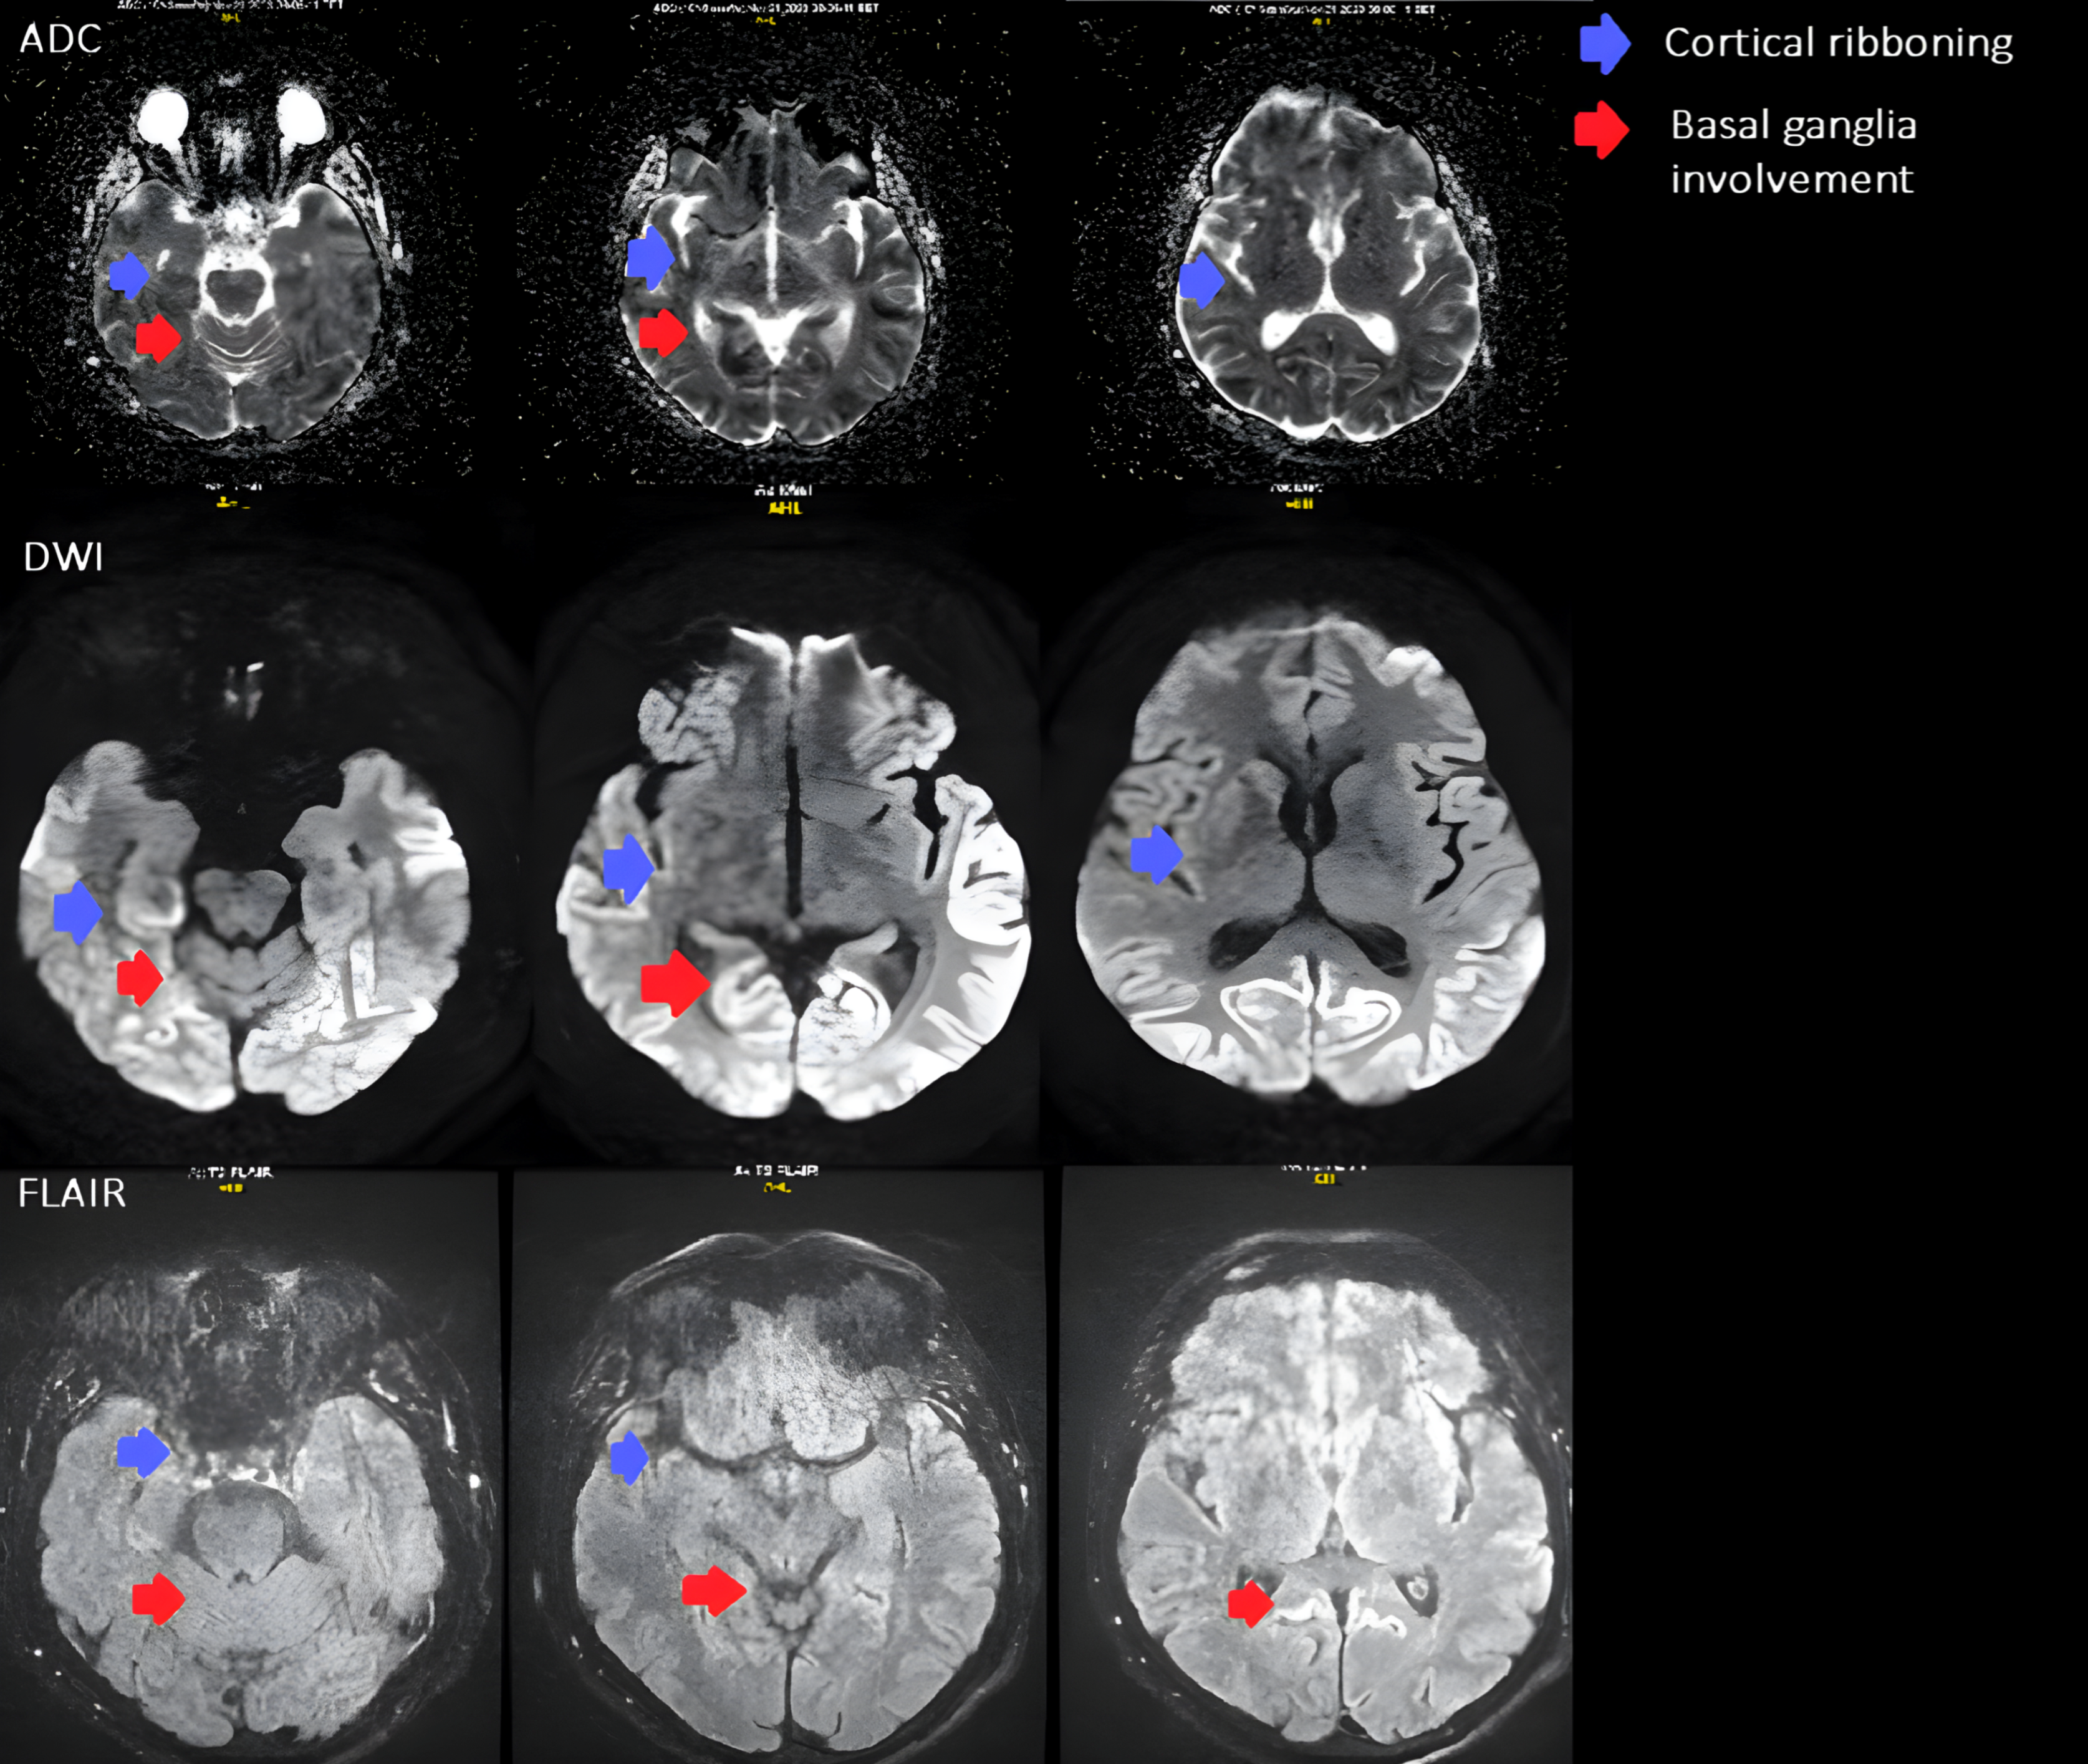

The diagnostic evaluation comprised an ECG revealing normosystolic atrial undulation, and biochemical assessments confirming normal renal, hepatobiliary, and endocrine functions with no abnormalities in infectious or haematological profiles. Pulmonary tests were unremarkable, a fundus examination was conducted, and HIV testing returned negative. Further cardiovascular reassessment showed no evidence of a thrombus on the mitral valve prosthesis, and given the mismatch with ischemic clinical signs, a repeat CT was performed, but it remained inconclusive. The encephalography revealed disorganized and slowed bioelectric activity across all brain regions, particularly in the centro-temporo-occipital areas (more pronounced on the right), absence of physiological alpha rhythm waves, and generalized epileptiform activity in both hemispheres. Suspecting rare diseases and to explore potential demyelinating processes, an MRI was subsequently conducted. MRI revealed diffusion restriction in the cerebral cortex, primarily affecting the parietal, occipital lobes and cingulate gyrus, with less involvement observed in the fronto-temporal lobe, right caudate nucleus, and anterior putamen. The MRI findings supported the probable diagnosis of Creutzfeldt–Jakob disease (Figure 1).

MRI revealed diffusion restriction in the cerebral cortex, predominantly in the parietal, occipital lobes, and cingulate gyrus, with lesser involvement in the fronto-temporal lobe, right caudate nucleus, and anterior putamen. Additionally, there were signs of previous microhemorrhages in the temporo-parietal areas, indicated by hemosiderin deposits.

Figure 1. Axial brain MRI shows signal changes typical of Creutzfeldt–Jakob disease. Restricted diffusion is seen in the parietal and occipital cortices (cortical ribboning, blue arrows) and in the basal ganglia, involving the caudate nucleus and anterior putamen (red arrows). The ADC maps demonstrate reduced diffusion, and corresponding hyperintensities on FLAIR confirm the same areas of involvement.